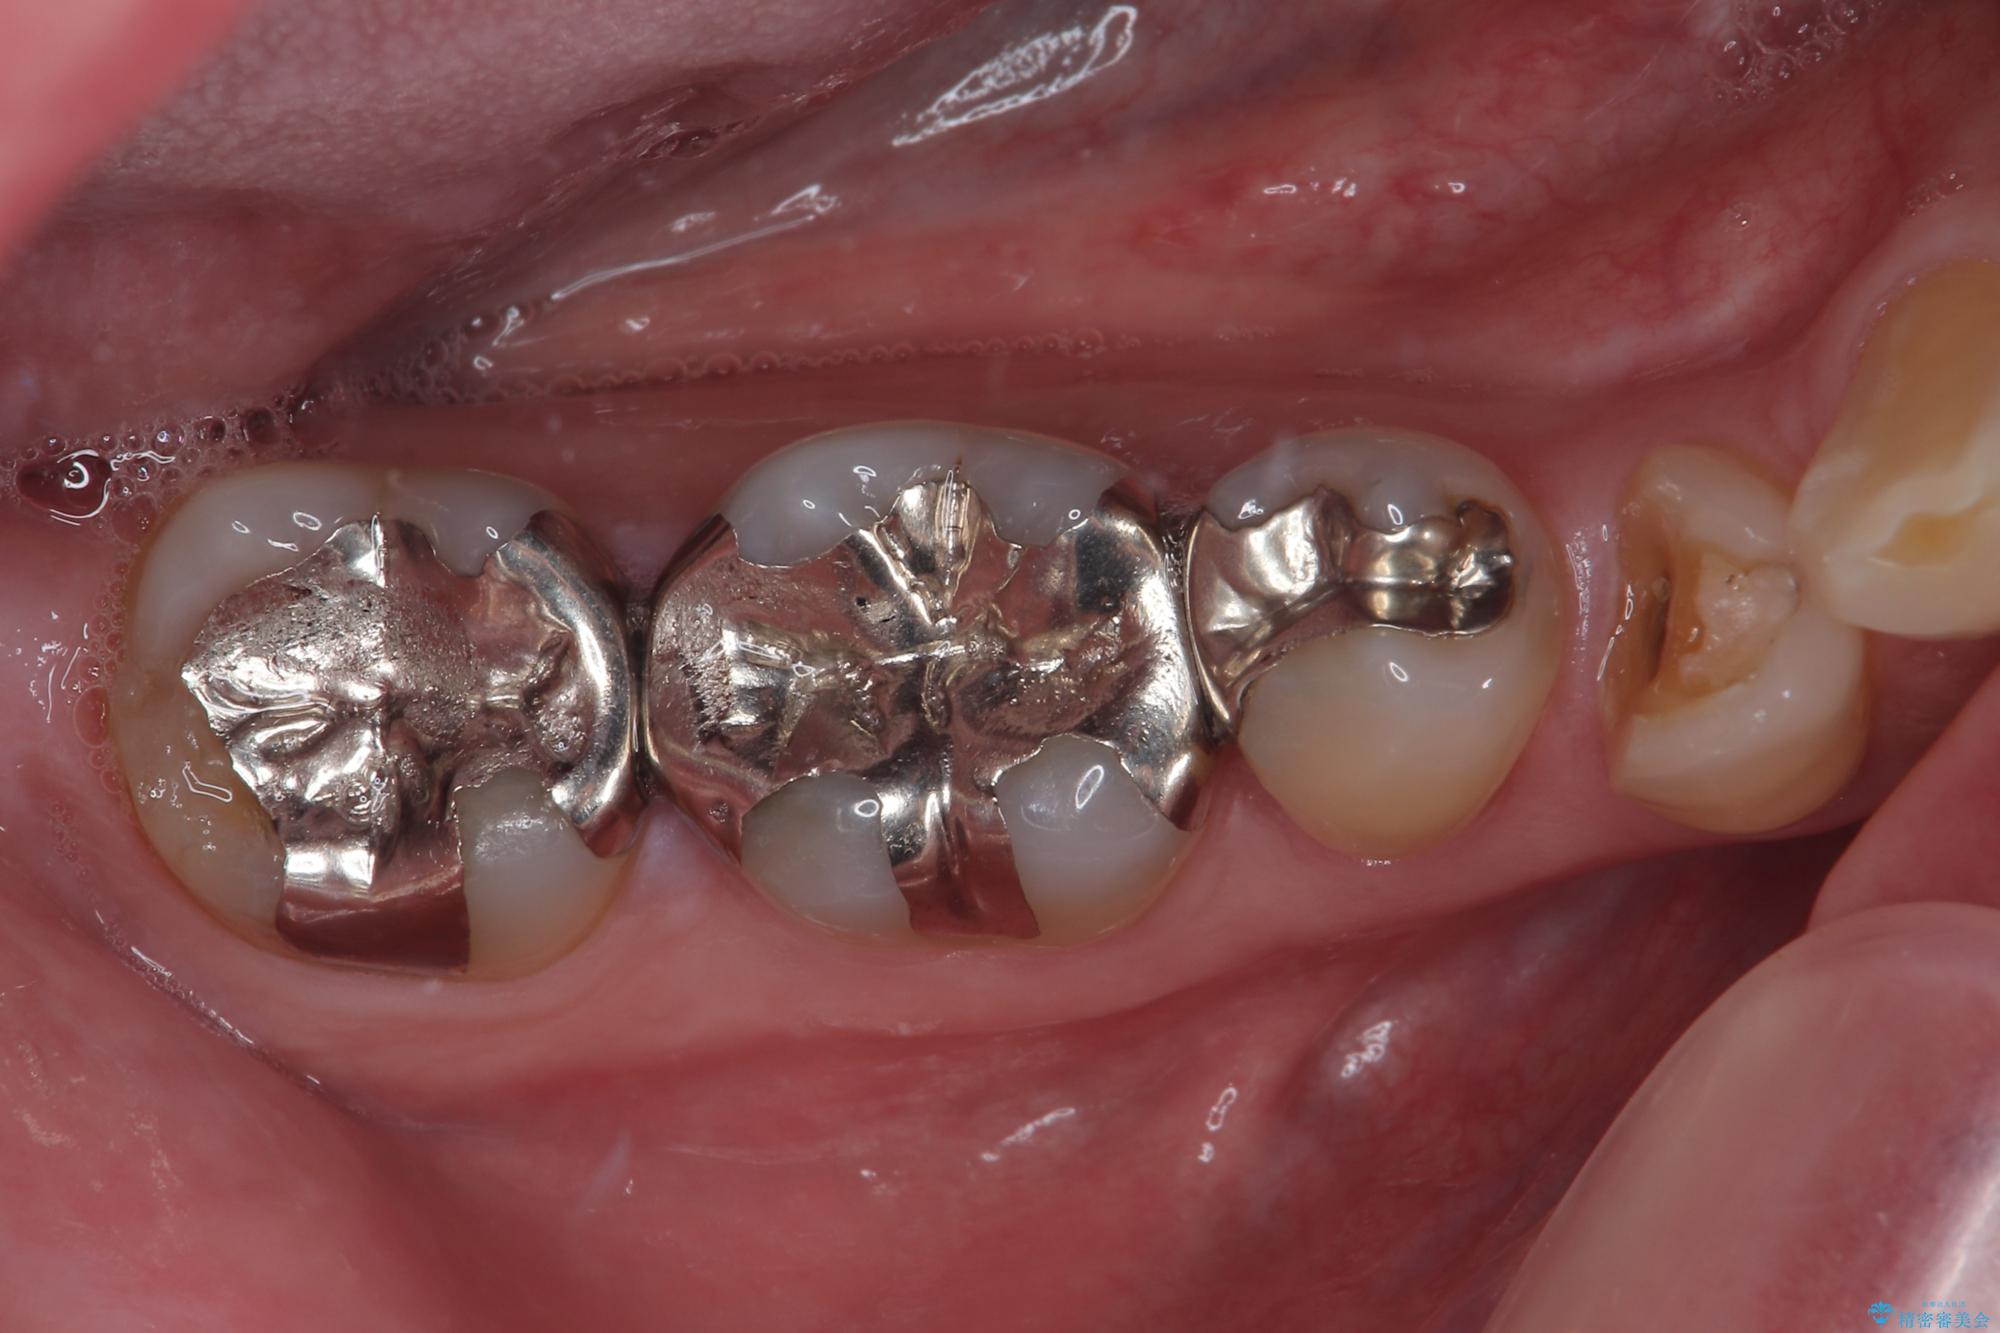

- 右下の銀歯が取れたとのことで来院された患者様です。以前にも取れていたところで、メタルインレーの不適合も認めていたため、次回外れたらオールセラミッククラウンにやり替えていくことを説明していたため、オールセラミッククラウンによる補綴治療を行っていくことにしました。

拡大鏡視野下で虫歯を除去しオールセラミッククラウンに適した形に整えました。

審美面、機能面共に満足していただけました。

順次、後ろにある不適合のメタルインレーの部位をやり替えていく予定です。